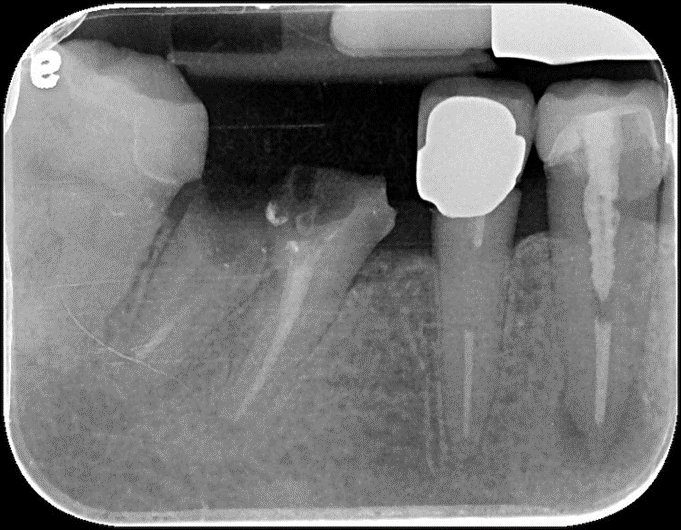

拔牙及補骨

補骨5個月後追蹤